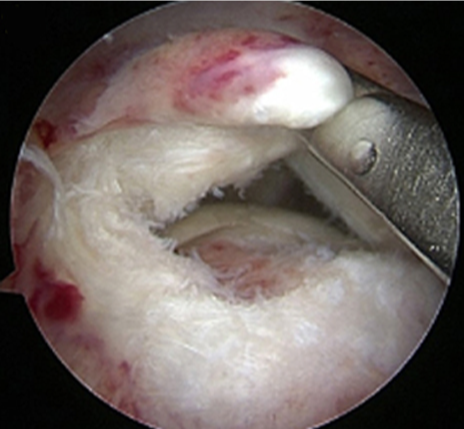

관절내시경을 통해 손상되고 찢어진 회전근개를 다듬어 주고 필요하다면 봉합까지 해주는 수술이 시행됩니다.

찢어지고 파열된 회전근개 모습

관절내시경 수술 후

회전근개를 다듬고 봉합해준 모습

ㆍ환자 동의를 받은 자료이며, 이미지 사진은 실물과 다를 수 있습니다.

ㆍ2016.09.27 관절내시경 당일 치료 전, 후 사진입니다.